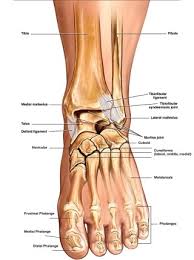

발목 통증은 발목을 지탱해주는 뼈, 연골, 근육등에 대한 문제로 발생할 수 있습니다.

아킬레스건이란 발목 뒤꿈치쪽에 있는 발목과 종아리를 연결하는 조직입니다.